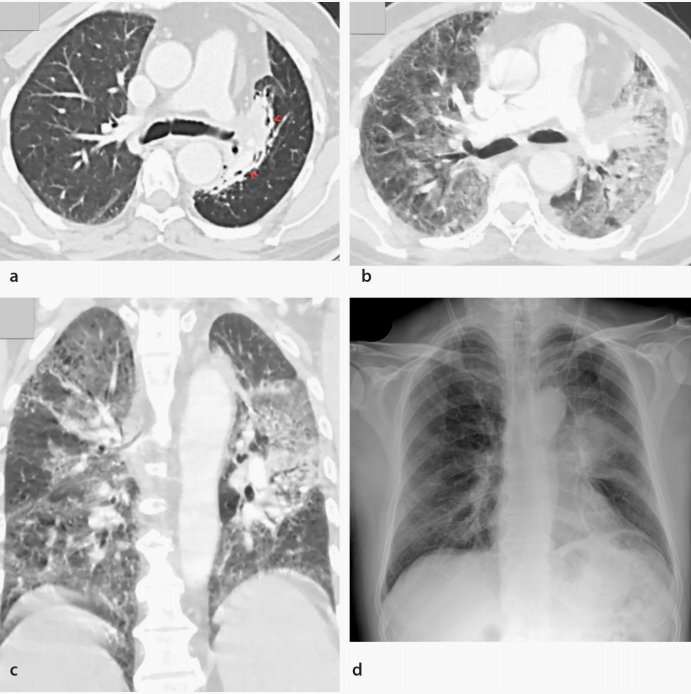

DAD或急性间质性肺炎(AIP)是罕见的DILD模式,通常与急性临床症状和影像学上弥漫性肺部浸润相关。组织病理学上以II型肺泡细胞坏死、肺泡水肿和肺泡内皮细胞坏死为特征。DAD影像学特点为GGO或相关实变区通常累及肺大部分甚至全部区域(图5)。在DAD中,常可见以小叶间隔和小叶内线增厚为特征的“铺路石征”模式。此外,如果不及早治疗,其他模式(如OP)可能会进展为DAD。DAD-AIP也可见于肺外原因,如急性呼吸窘迫综合征、败血症和输血相关的急性肺损伤。

图5 52岁转移性非小细胞肺癌的男性患者出现Pembrolizumab引起的DAD。(a)基线轴向胸部CT示左肺门肿块伴放射治疗引起的病灶周围纤维化(箭头)。(b)轴位和(c)冠状位胸部CT图像,Pembrolizumab开始使用两周后,CT示影响到大多数肺部区域的弥漫性GGO,提示DAD。停用Pembrolizumab,患者住院,并开始1 mg/kg/天的泼尼松治疗。(d)两个月后胸片示肺部阴影消退。